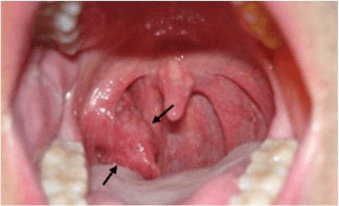

El virus del papiloma humano y su relación con cáncer de boca y faringe

El cáncer de cabeza y cuello es el sexto cáncer más común en todo el mundo. Cada año, casi 650 000 pacientes en todo el mundo son diagnosticados con cáncer de cabeza y cuello y casi el 40 % de estos pacientes mueren a causa de esta enfermedad. Aproximadamente el 90 % son carcinomas de...